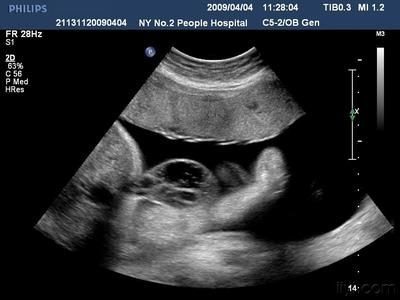

据介绍,经过中山大学法医鉴定中心鉴定,根据法医系统尸体解剖检验,邹某之女体表及内部器官未发现机械性损伤征象,故可排除机械性暴力作用致死。结合案情分析,邹某之女属未成熟儿,符合宫内窒息死亡。

对此,原告方则反驳,根据中山大学法医鉴定中心的医学鉴定显示,邹某之女的尸体体表及内部器官未发现机械性损伤征象,故可排除机械性暴力作用致死,因此可以排除与医生操作有关。不过,邹某的辩护人则认为,医学鉴定只是说排除机械性暴力作用致死,并不能排除与医生吕某某的操作有关。